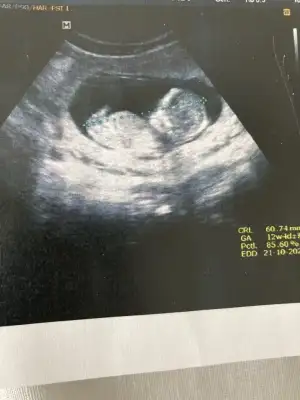

Ikra meyra Ikra meyra canım benim ve ablamın cinsiyetlerini doğru bildin ikimizde soğum yaptık 3 ay oldu🥰 buda baska bi ablamın 5+5 haftalık bakar mısın acaba 🌸

Eklentiler

• FCEFFB52-EB51-4B8C-9357-912DFE1E69C7.webp

FCEFFB52-EB51-4B8C-9357-912DFE1E69C7.webp

16 KB · Görüntüleme: 54

• 11B140B8-FEA3-4682-9F99-32BD9BCE56A0.webp

11B140B8-FEA3-4682-9F99-32BD9BCE56A0.webp

16,7 KB · Görüntüleme: 59

Sağlıkla büyütün evlatlarinizi 🤲 😍 Karından bakıldı ise kız vajinal ise erkek tabiki en iyi 11 12 13 haftalar olmalı 🤗